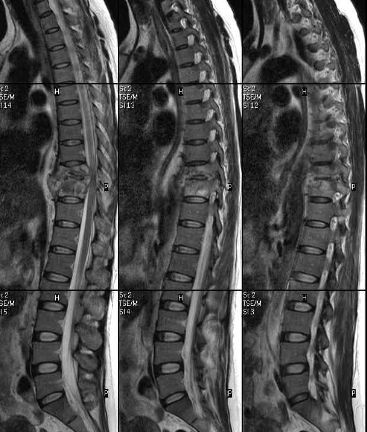

脊柱转移瘤胸椎

脊柱转移瘤胸椎,脊柱转移瘤

脊柱转移瘤

脊柱转移瘤图片

转移性脊柱肿瘤图片

脊柱转移瘤磁共振图片

腰椎转移瘤核磁图片